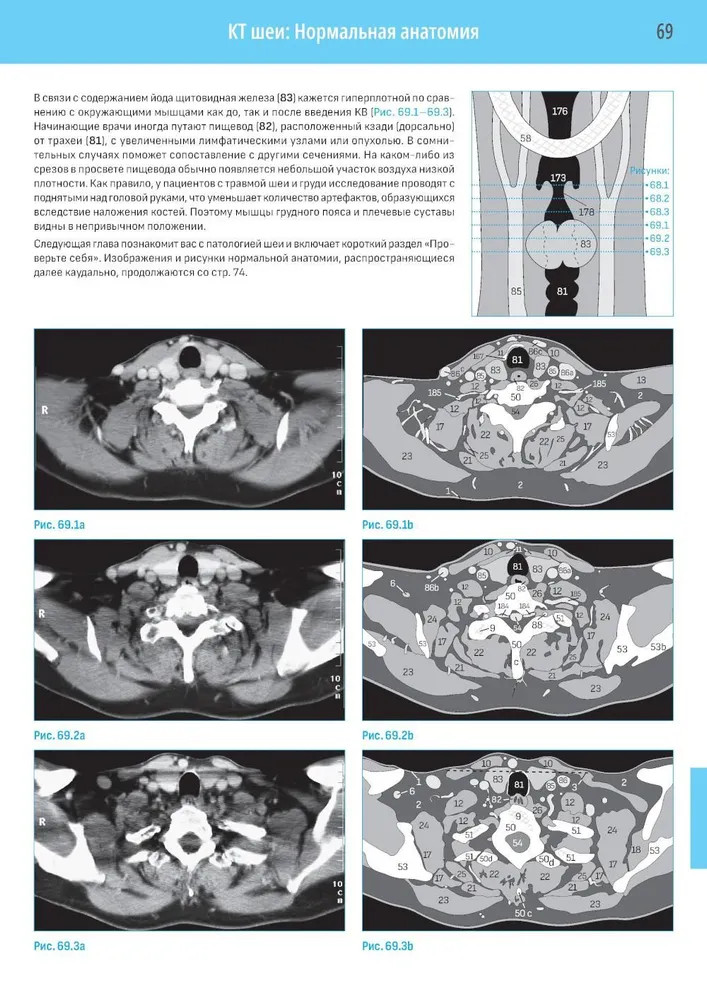

💳 Оплатить за товар можно при получении 🇰🇿 Есть бесплатная доставка по Казахстану от 1 дня 🎁 Копите бонусы с каждой покупки Четвертое издание на русском языке представляет собой базовый курс подготовки и переподготовки специалистов по компьютерной томографии по международным стандартам. Представлен систематизированный подход к анализу компьютерных томограмм всех частей тела. Описаны самые современные методики, включая КТ-ангиографию, КТ с двумя источниками и ПЭТ/КТ. Книга содержит более 1000 высококачественных иллюстраций — компьютерных томограмм со схемами, иллюстрирующими их анатомический смысл и диагностическое значение. Каждая глава содержит задания для самоконтроля, что позволяет читателю самостоятельно организовать и контролировать процесс обучения. |